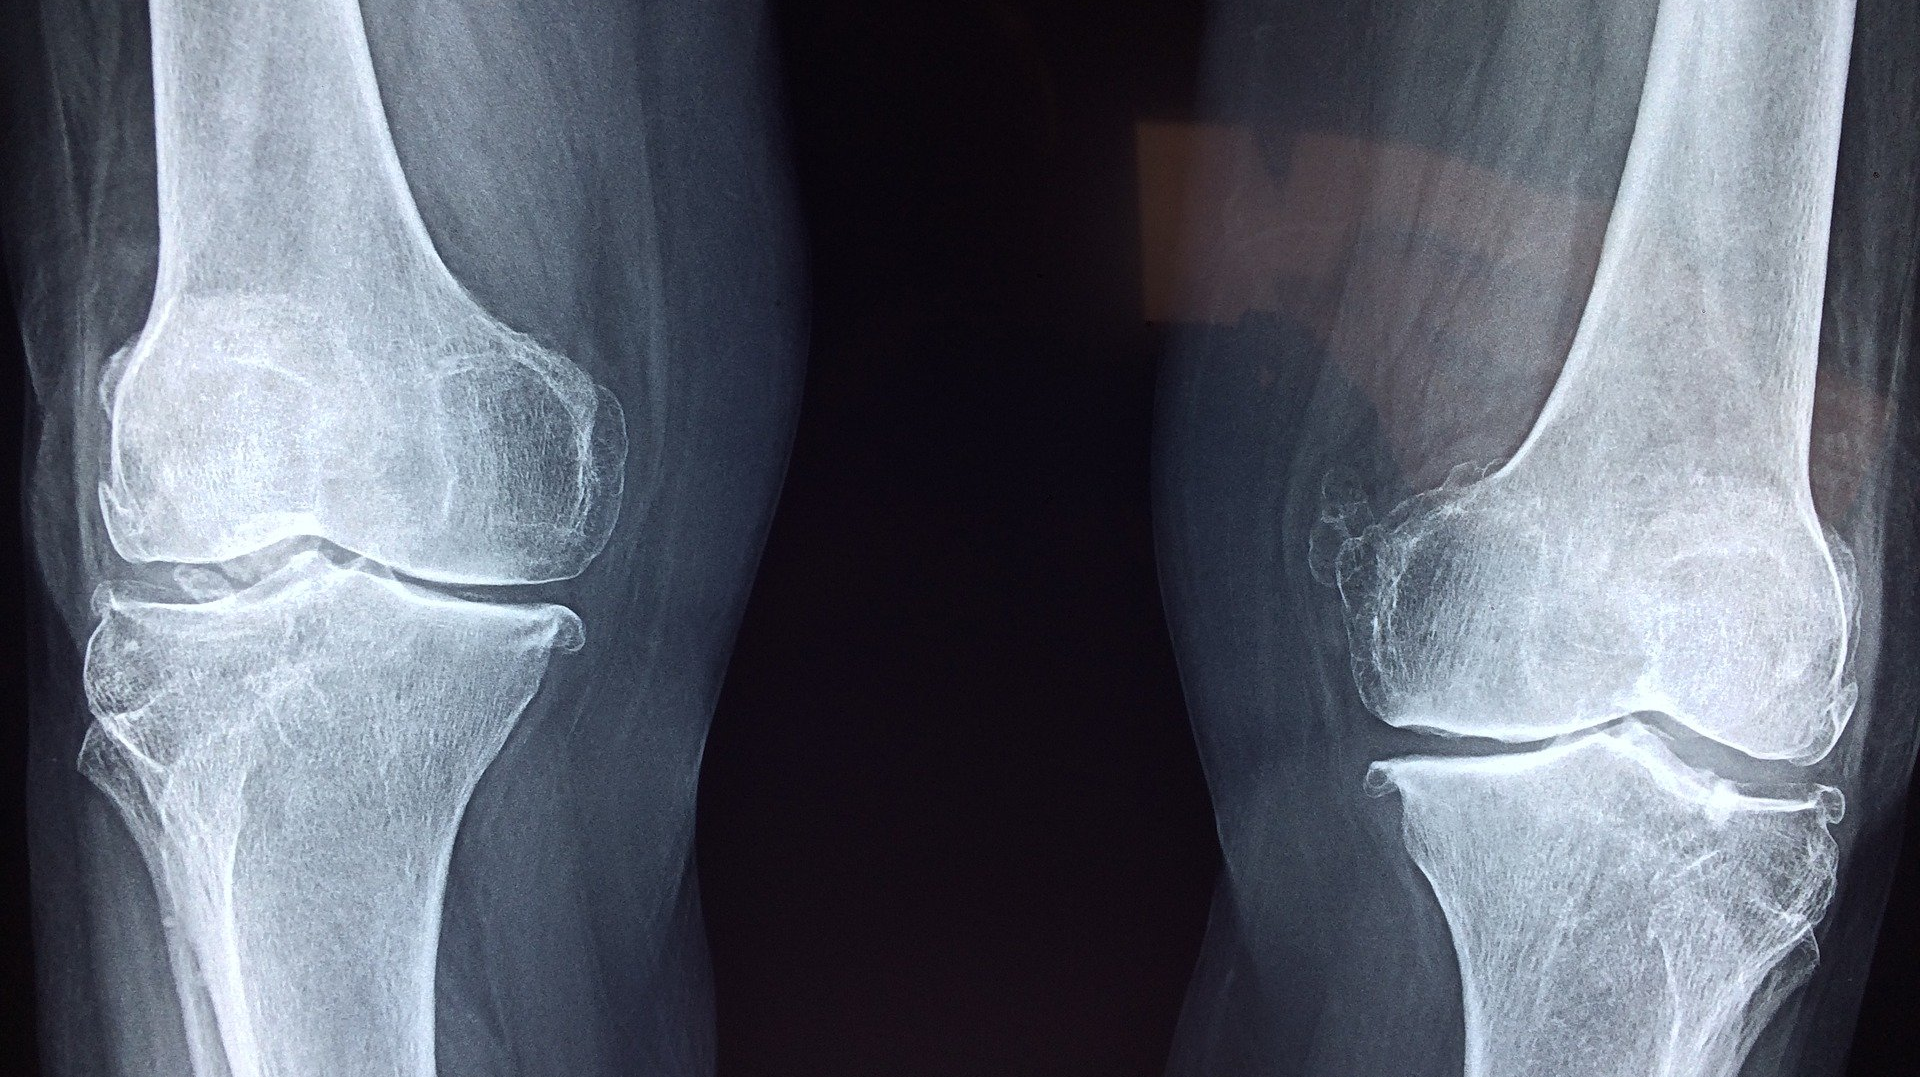

The American Joint Replacement Registry (AJRR), the cornerstone of the American Academy of Orthopaedic Surgeons (AAOS) Registry Program, released its 2020 Annual Report on hip and knee arthroplasty patient outcomes.

The Annual Report, released in conjunction with the first day of the American Association of Hip and Knee Surgeons’ (AAHKS) 2020 Annual Meeting, includes findings from 1,897,050 hip and knee arthroplasty procedures performed between 2012 and 2019, representing an overall cumulative procedural volume growth of 24.4 percent compared to the previous year.

The Annual Report marks the seventh annual report from the AJRR. With the collection and reporting of this data, the report aims to provide valuable information to orthopaedic surgeons, hospitals, ambulatory surgery centers, device manufacturers, payers, and most importantly patients. The 2019 data paved the way for the AJRR to exceed two million procedures as of June 26, 2020, providing even more actionable data to improve patient care and outcomes.